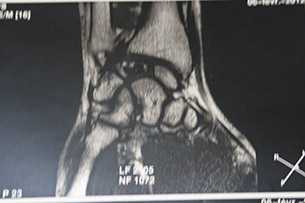

Некроз полулунной кости на МРТ

Большинство пациентов жалуются на боль запястье, усиливающуюся при нагрузке. При осмотре определяется болезненность в проекции полулунной кости. Первые шаги для диагностики болезни Кинбека — это сбор анамнеза, осмотр и рентгенограммы. Иногда требуются дополнительные исследования, наиболее информативным из которых является магнитно-резонансная томография. Именно МРТ позволяет выявить нарушение кровоснабжения полулунной кости, когда еще нет изменений на рентгенограммах. Также могут применяться компьютерная томография или остеосцинтиграфия.